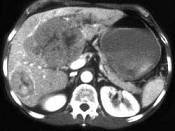

女,67岁,右上腹疼痛,消瘦4个月余,CT检查如图,最可能的诊断是 ( )A、肝转移瘤B、肝囊肿C、肝脓肿D、肝癌E、肝血管瘤

问题 女,67岁,右上腹疼痛,消瘦4个月余,CT检查如图,最可能的诊断是 ( )

选项 A、肝转移瘤 B、肝囊肿 C、肝脓肿 D、肝癌 E、肝血管瘤

答案 D